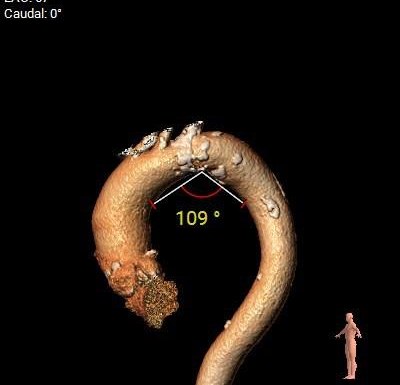

弓角弓距及瓣环角度

外周入路